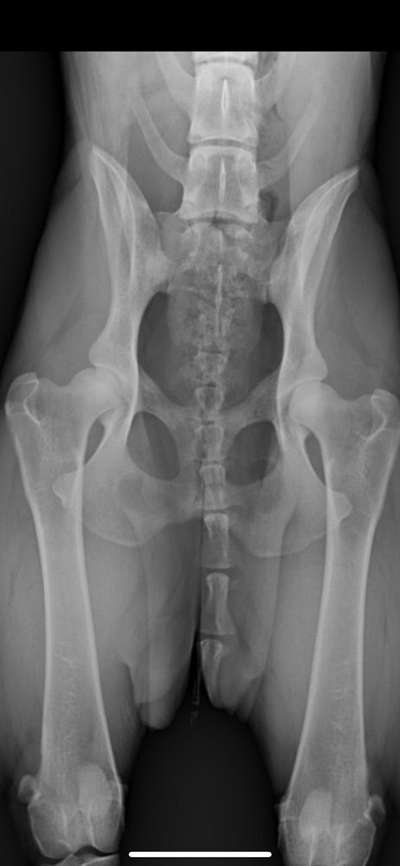

Hab Röntgen Bilder für euch. Lagerung nicht perfekt und bin gespannt was der Doktor zum LÜW sagt...

1